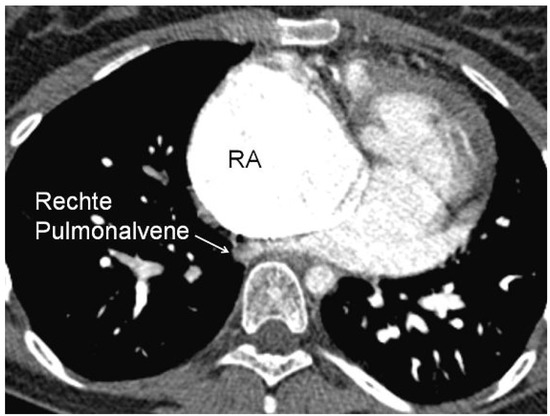

Die Fontan-Konversion—Oder das Schicksal, Die Erste zu Sein

We report the case of the first patient with tricuspid atresia in whom an “old-fashioned” Fontan operation with an atriopulmonary anastomosis was performed in our hospital 18 years ago. Complications of the former “classical” Fontan circulation can include progressive right atrial dilatation leading [...] Read more.

We report the case of the first patient with tricuspid atresia in whom an “old-fashioned” Fontan operation with an atriopulmonary anastomosis was performed in our hospital 18 years ago. Complications of the former “classical” Fontan circulation can include progressive right atrial dilatation leading to tachyarrhythmias, flow energy loss, obstruction of pulmonary veins, right atrial thrombi and the formation of pulmonary arteriovenous fistulas. In order to palliate our patient from recurrent atrial tachyarrhythmias and increasing haemodynamic disturbances, the previous “old-fashioned” Fontan circulation was surgically revised and converted according to a “modern” type of extracardiac Fontan circulation with additional anti-arrhythmic procedures. The post-operative course was uneventful. After recovery from surgery, the patient’s quality of life improved. She is free from atrial tachycardias and shows an increased exercise capacity. We will briefly discuss the complications of the classical Fontan circulation and the possible risks of the Fontan conversion. After having been the first Fontan patient in our center, our patient was again the first to require a major revision of its circulation. Full article